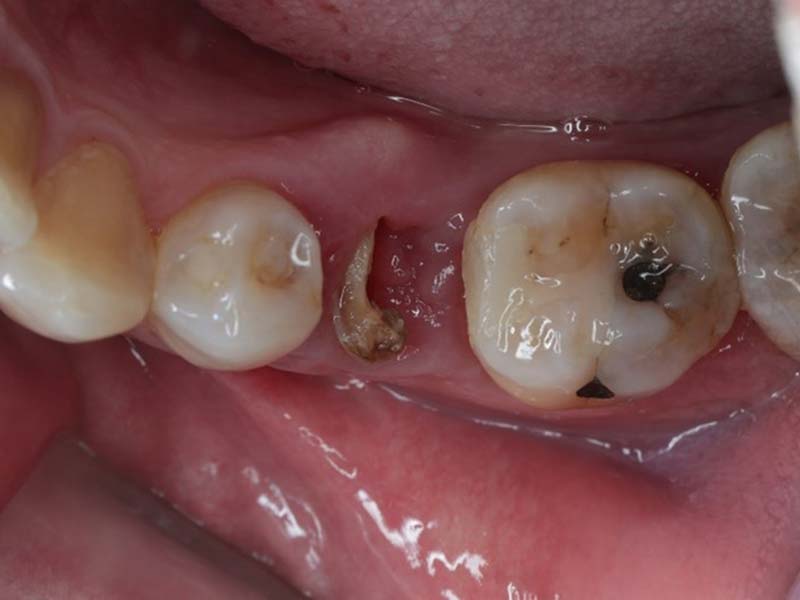

殘餘牙齒拔除後,待傷口癒合,使用口掃機取得全口3D模型,製作數位導板和治療計畫,精準定位將組織及骨膜切開,將植體鎖入凹槽並在齒槽骨裡面,讓植體周圍牙肉保持在最佳狀態。中間等待約3-6個月的時間,讓植體與骨肉整合,待復原完成後就可以取模製作植牙假牙了。

裝上植牙假牙